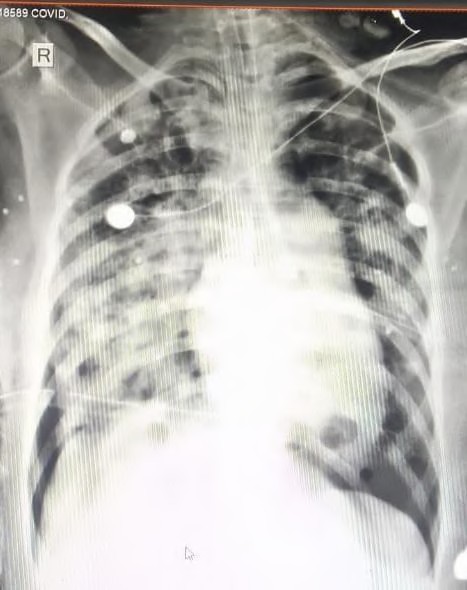

Fig. 2: B/l pneumothorax with ICD in covid 19 patient